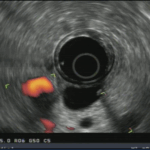

Frontiers in Endoscopy, Series #98

Endoscopic Ultrasound-Guided Therapy for Gastric Varices: Current Evidence and Emerging Perspectives

1. Introduction Gastric varices (GV) are a serious complication of portal hypertension, present in about 20% of cirrhotic patients compared to up to 85% with esophageal varices (EV).1,2 Though less […]